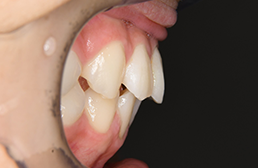

初診時

FP・IOP

口腔内所見 over jet 7.5mm,over bite 3.5mm,大臼歯関係はⅡ級 。Hellmanのdental ageはⅢAであり上突咬合を呈していた。